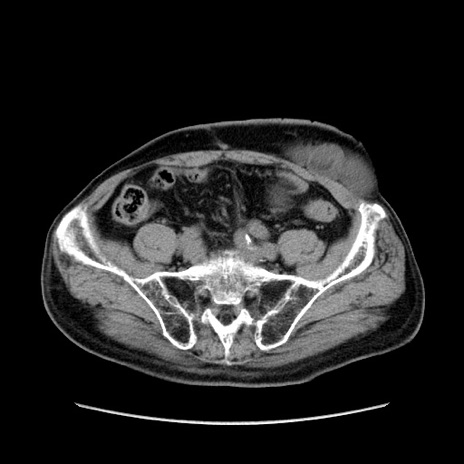

症例24(横断像)

【症例】80歳代男性

【主訴】左側腹部痛、嘔吐

【現病歴】本日早朝より左腹部に痛みあり。昼頃嘔吐認めたため、救急要請。

【既往歴】直腸癌(Mile手術)、胆摘

【身体所見】意識清明、BT 35.9℃、BP 221/93mmHg、SpO2 97%(RA) 、腹部:左ストーマ周囲に限局性の腹部膨隆あり。 膨隆部自発痛・圧痛あり・軟。

【データ】WBC 7700、CRP 0.09